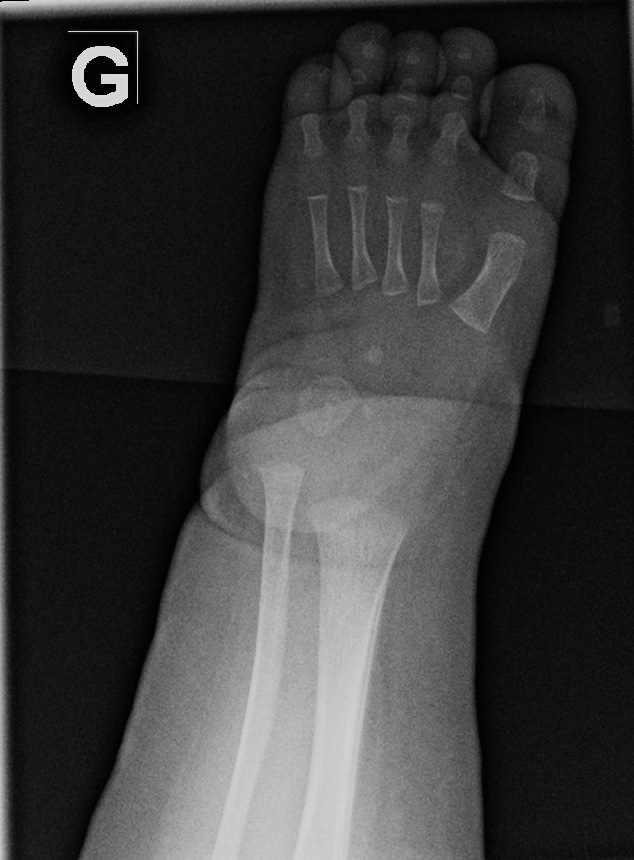

0-hour-old male:

Feet deformity.

On the right side, the anteroposterior talo-calcaneal angle (Kite's angle) is decreased to 7° (normal between 20 and 40°). On the lateral view of Turco, the talo-calcaneal angle is 30° (normal over 35°). In short, on the anteroposterior view, the talus and calcaneus are more parallel than expected (normaly they are diverging).

On the right anteroposterior view, the talus-1st metatarsal angle is measured at -7° (normal between 0 and 20°). The 1st metatarsal is medial to the talus because of the forefoot deviation in varus and adductus.

On the left side, the talus is not ossified enough to take measurements. Global alignment, however, suggests a left club foot of similar severity than the right.